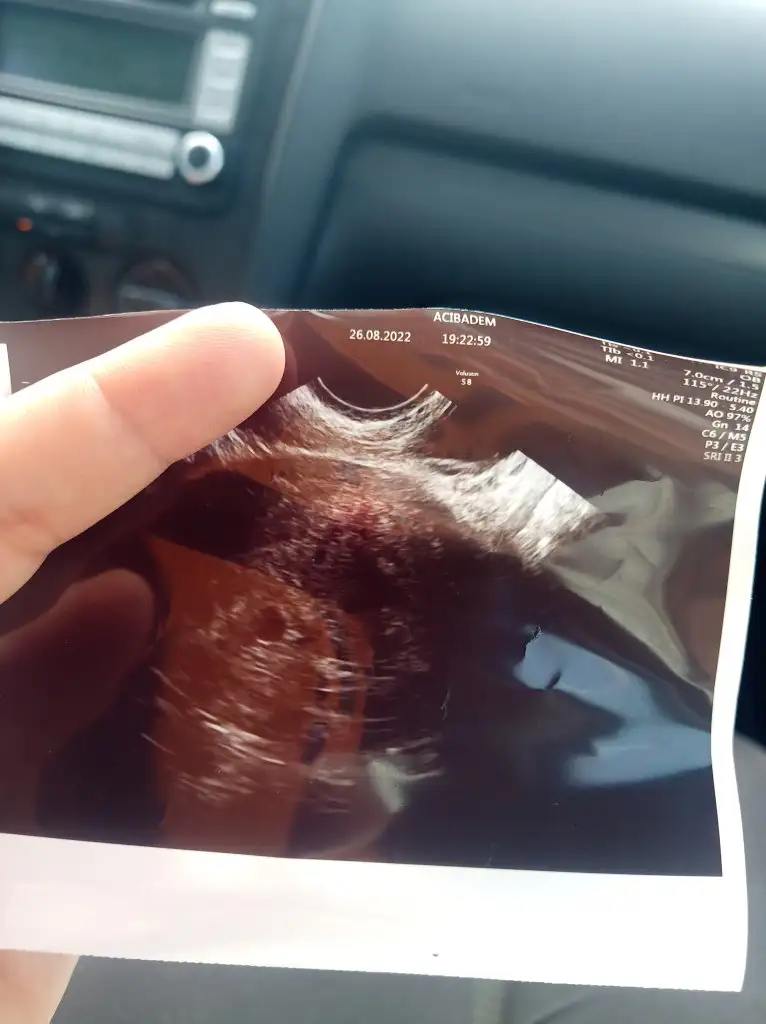

mutluluk gözyaşların olsunAyrintilari yaziyorum hemen hoca alttan bakti direk ayin 6 sina kalp atisi icin gun verdi ugrasmamak icin direk alttan bakti ilaclara aynen devam dedi ekstra biseye gerek yok dedi kiz aklim darma duman aglamaktan![]()

Gozunaydin devamı gelsin ins hayırlaAyrintilari yaziyorum hemen hoca alttan bakti direk ayin 6 sina kalp atisi icin gun verdi ugrasmamak icin direk alttan bakti ilaclara aynen devam dedi ekstra biseye gerek yok dedi kiz aklim darma duman aglamaktan![]()